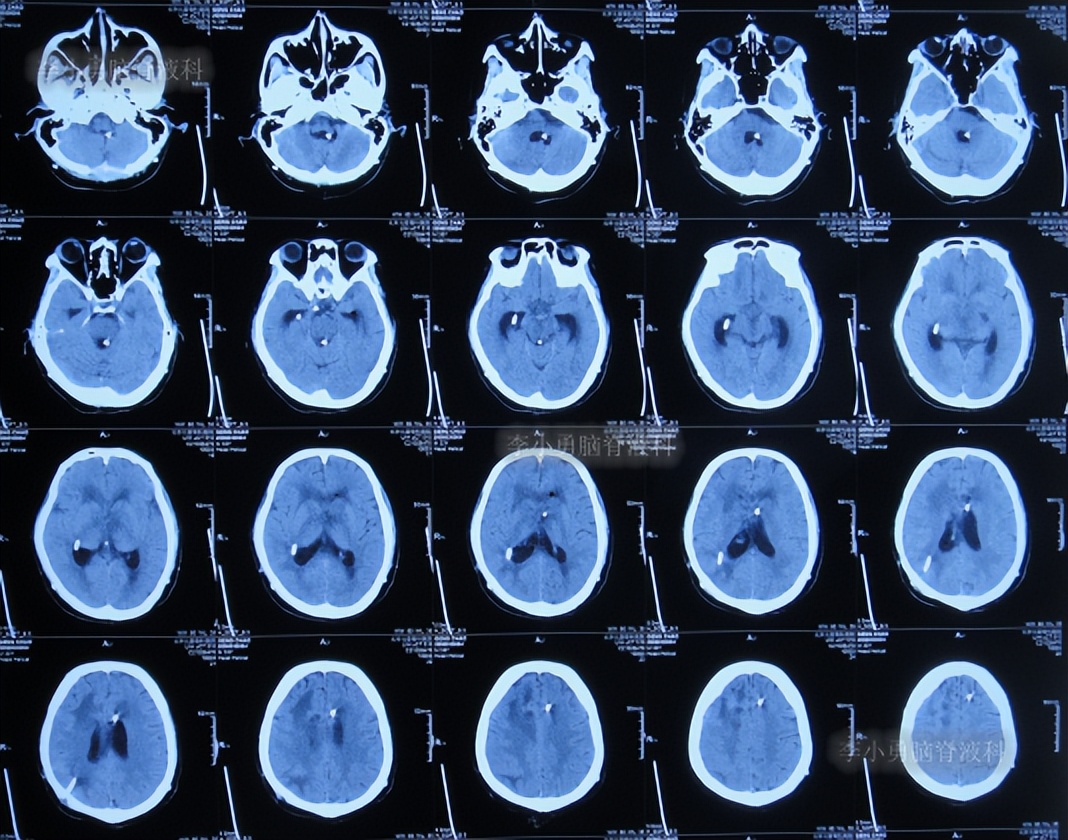

二、第1次在李小勇脑脊液科治疗过程和结果

2020年6月4日(脑囊虫切除术+第三脑室造瘘术后2年5个月,2次脑室腹腔分流术均堵管,期间历经5次住院但脑积水仍反复复发)住入李小勇脑脊液科,入院时:神志朦胧,饮食差,问答有误,自己站立不稳,双眼对视(图-19);既往史:口服抗癫痫药物,青霉素过敏。头颅CT示鞍上占位术后,脑室内可见引流管,脑室系统扩张(图-20)。

图-20:2020年6月4日头颅CT